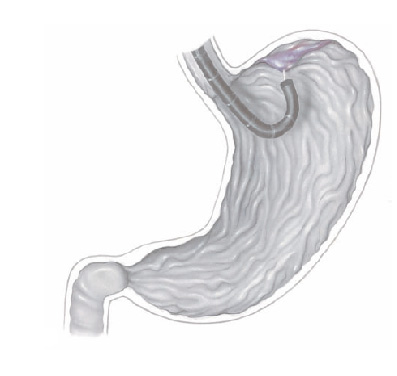

Pacientes que têm o objetivo de emagrecer, podem ter como alternativa a passagem de um balão intragástrico. A passagem do balão é realizada por endoscopia e o procedimento dura cerca de 20 a 30 minutos.

Passagem de Balão Intragástrico

1. O balão intragástrico é introduzido desinsuflado durante a endoscopia e colocado no estômago.

2. Um líquido azul (azul de metileno diluído em soro fisiológico) é colocado dentro do balão através de uma válvula. O volume varia entre 500-700 ml.

3. O aparelho de endoscopia é removido e o balão intragástrico pode ser deixado por um período de até 6 meses.

O balão intragástrico ocupa um espaço dentro do estômago e o paciente fica com sensação de plenitude e saciedade precoce. Em outras palavras, sobra menos espaço para os alimentos, diminuindo o volume ingerido nas refeições.

Pacientes que têm o objetivo de emagrecer, podem ter como alternativa a passagem de um balão intragástrico. A passagem do balão é realizada por endoscopia e o procedimento dura cerca de 20 a 30 minutos.

Passagem de Balão Intragástrico

1. O balão intragástrico é introduzido desinsuflado durante a endoscopia e colocado no estômago.

2. Um líquido azul (azul de metileno diluído em soro fisiológico) é colocado dentro do balão através de uma válvula. O volume varia entre 500-700 ml.

3. O aparelho de endoscopia é removido e o balão intragástrico pode ser deixado por um período de até 6 meses.

O balão intragástrico ocupa um espaço dentro do estômago e o paciente fica com sensação de plenitude e saciedade precoce. Em outras palavras, sobra menos espaço para os alimentos, diminuindo o volume ingerido nas refeições.